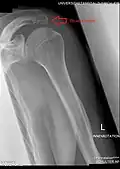

Os acromiale

The acromion has four ossification centers called (from tip to base) pre-acromion, meso-acromion, meta-acromion, and basi-acromion. In most cases, the first three fuse at 15–18 years, whereas the base part fuses to the scapular spine at 12 years. However, in between 1% and 15% of cases, this osseous union fails and the acromion remains separate as an accessory bone. This condition is referred to as os acromiale, but rarely causes pain. Earlier estimates of its prevalence were as low as 1.4%, and this higher estimate was made by Sammarco in the year 2000, based on radiographic and anatomical studies.[6][7]

Radiograph of the shoulder showing an os acromiale